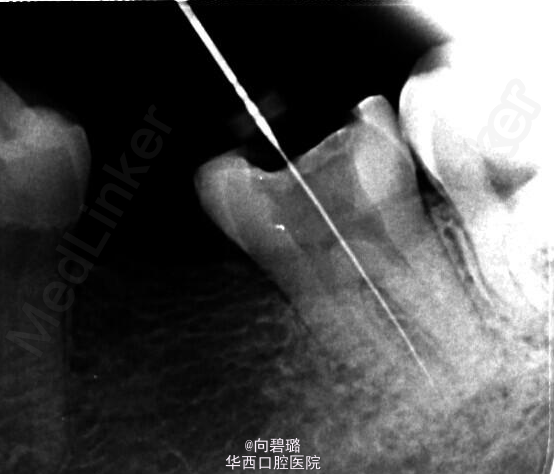

37牙根管预备过程中,由于其近中根疏通不畅,照片,牙胶失踪疑似底穿,加大投照角度依然如此。那么我们在临床工作中应该怎么样辨别底穿与否?首先X片是一个很直观的图像,一般来说可以从X片上看出来底穿与否(牙槽中隔是否有破坏或炎症性吸收),但是遇到磨牙三个根,四个根的情况时,由于投照角度的问题可能会不太好辨别,这个时候可以扩大探针看是否有出血,病人是否感觉疼痛,这都是一些辨别的手段。(来自:http://blog.kq88.com/88868.html)